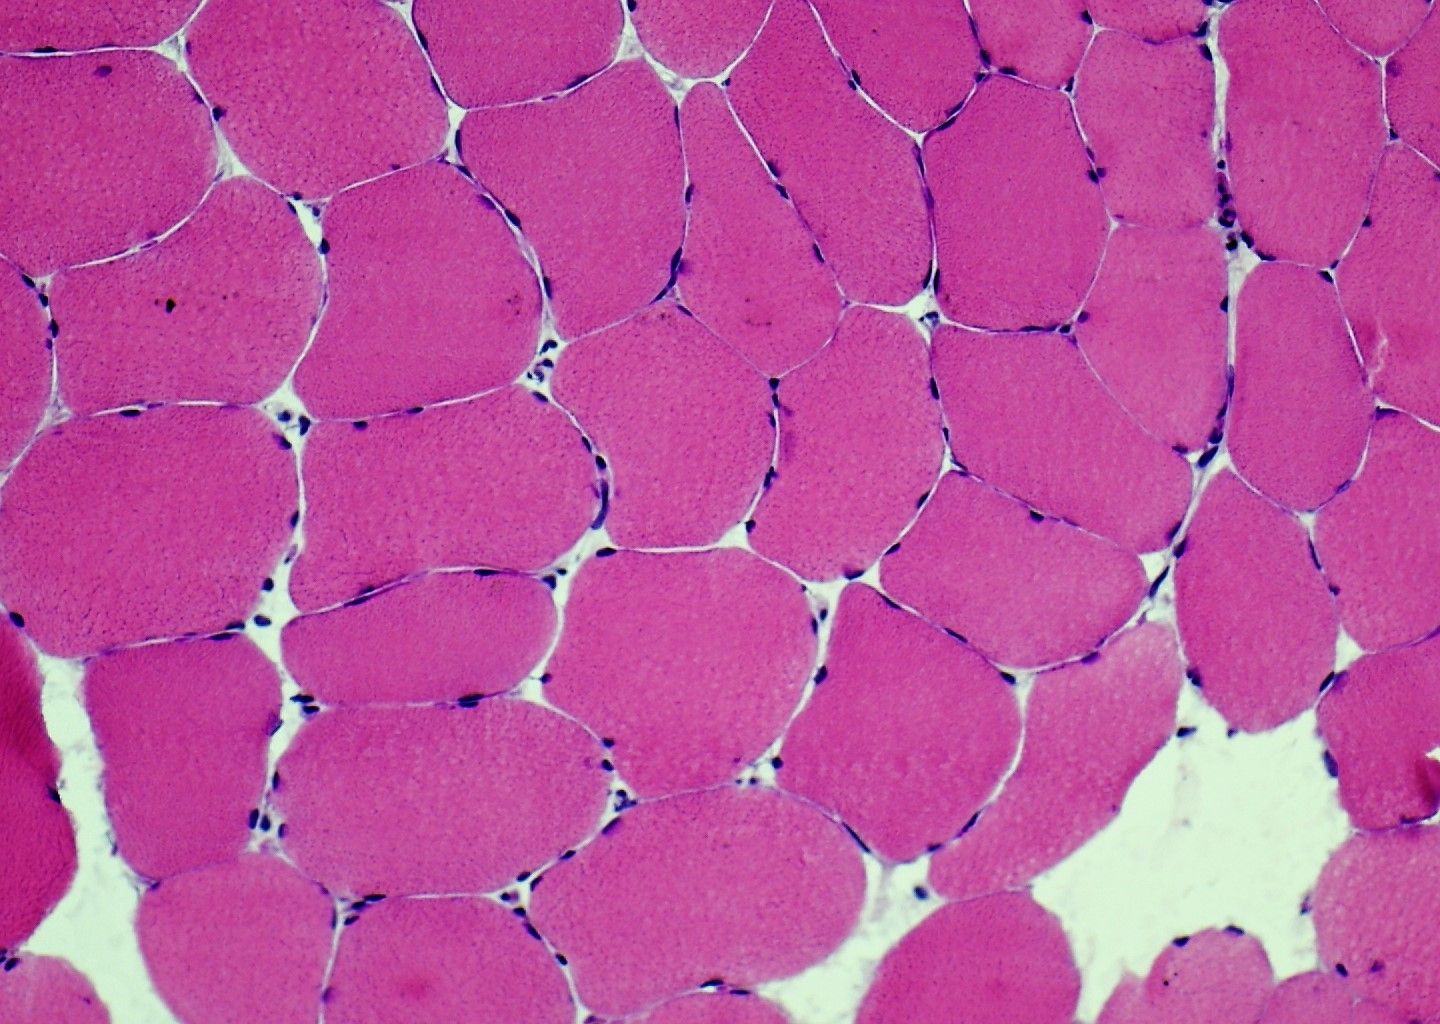

- ਅਨੁਕੂਲ ਅਤੇ ਉਪ-ਅਨੁਕੂਲ ਰੰਗਾਈ ਦਿਖਾਉਣ ਵਾਲੇ ਰੰਗ ਚਿੱਤਰਾਂ ਦੀ ਔਨਲਾਈਨ ਲਾਇਬ੍ਰੇਰੀ